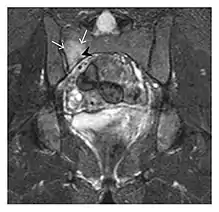

Insufficiency fractures

Insufficiency fractures occur in weakened bones. Although osteoporosis is a classic cause, other conditions resulting in bone demineralization are well-recognized risk factors. These include previous radiation therapy and chemotherapy, especially in a context of gynaecologic malignancy, chronic renal failure, chronic rheumatological diseases, and corticosteroid therapy. In long bones, chronic joint diseases such as rheumatoid arthritis are associated with angular deformity and flexion contraction, increasing the stress on the bone around the joints and, therefore, the risk of insufficiency fracture. Pelvic, sacral, and proximal femoral fractures are of increasing significance especially with the aging of the population.[1]

The sacrum is usually masked by overlapping bowel gas in conventional radiographs, and the subtle radiographic findings are usually nondiagnostic and even misleading. The characteristic "H" pattern has been correlated with biomechanical models of patient activities. The vertical parasagittal planes correspond to the region of maximal stress during walking, while the horizontal fracture develops later, secondary to the loss of lateral support by parasagittal fractures. MRI is the primary imaging technique in this case, with the most common MRI pattern showing bone marrow edema and a fracture line (Figure 12). Coronal views are quite contributive in sacral fractures, allowing the detection of the horizontal component, especially with fluid-sensitive sequences. Although the sacrum is the most commonly involved, pelvic insufficiency fractures are often multiple, and other typical locations should be mentioned.[1]

Proximal femoral fractures usually occur in osteoporotic patients, and their signs include subtle neck angulation, trabecular angulation, and subcapital impaction line. A frog-leg lateral view may be helpful if the greater trochanter is short enough. However, positioning can be difficult because of hip pain. In patients with strong suspicion of proximal femoral fracture and negative radiographs, MRI limited to coronal T1 W images and scintigraphy can be highly valuable (Figures 13 and 14). Such an option, with limited examination time, is cost-effective and allows reliable exclusion or confirmation of the diagnosis, preventing an unnecessary stay at the hospital or delayed treatment. Moreover, MRI helps to detect soft tissue abnormalities which are more frequently seen in femoral, acetabular, and pubic injuries than sacral lesions. Concomitant fractures are also frequently seen in typical pelvic sites.[1]

a

b

Figure 13: Partial osseous avulsion of the gluteal muscles at the greater trochanter in a 59-year-old man who presented with the right hip pain without a history of trauma. Lauenstein view and anteroposterior and radiographs (not shown) did not show an obvious fracture line or disruption of bony contours in the acetabulum or the right femoral neck. (a) Coronal T1-weighted MRI displays an incomplete fracture line extending partially from the greater trochanter (arrow). (b) Coronal short tau inversion recovery MRI shows heterogeneous hyperintensity in the same region (arrow) as well as hyperintensity within the gluteus medius and minimus muscles (arrowheads) consistent with tissue edema and hematoma.[1]